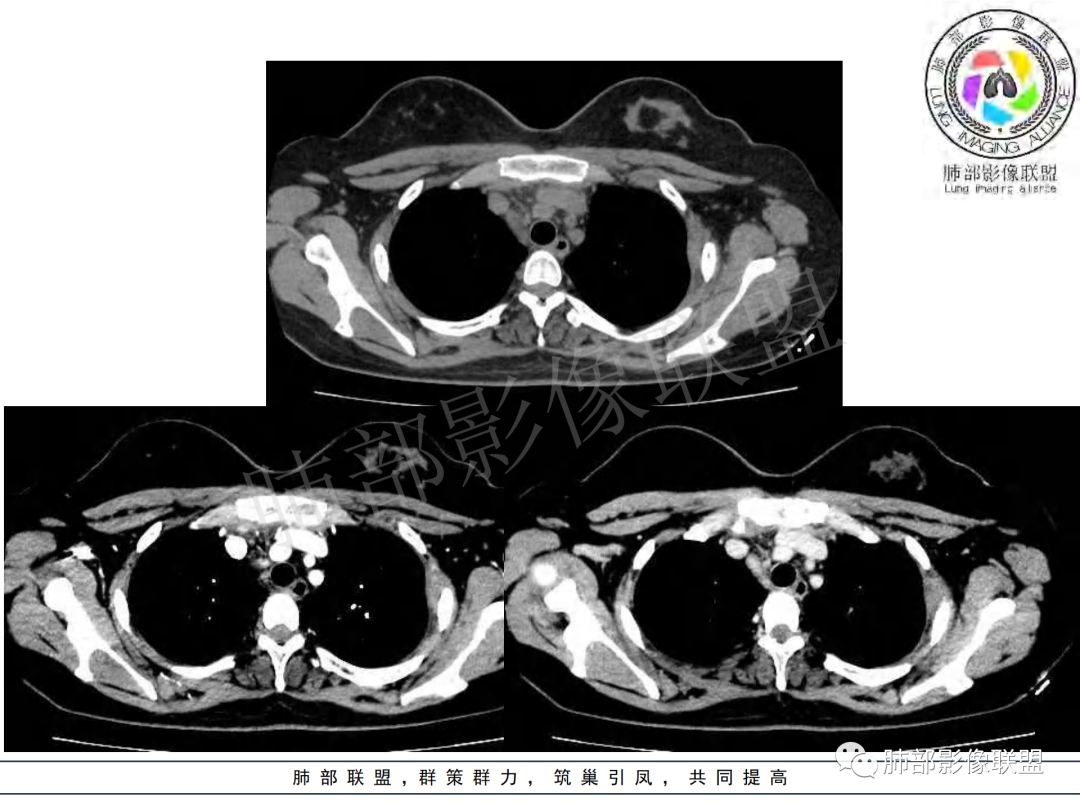

女,20,病程长达8月,发热、胸痛、右侧胸腔积液病史。胸部CT:右肺门旁不规则肿块影,右中间支气管腔内结节,纵隔多发淋巴结肿大;强化不均匀,灶性坏死灶,环形强化;右侧少量胸腔积液并局部肉芽肿样突起。年轻女性,长病程,多部位,考虑慢性炎症,结核?鉴别肿瘤。

年轻女性 大支气管占位恶性三件套 高强化 内部可见无强化区,无强化区与强化区内边界大部分不清晰,类癌、粘表、腺样囊性癌。首先考虑粘表   其次需要鉴别的有结核   这么大片的坏死 结节病可能性小

女性,20岁。高热、畏寒。右肺上叶近肺门区不规则肿块,周围斑点、片小结节影伴肿大淋巴结,肿块包绕并突入右主支气管腔内,增强后肿块不均匀强化,淋巴结环形强化中心低密度,考虑结核。

纵隔肺门及两侧胸膜强化结节,支气管管腔不通畅。结核能解释临床及影像,就是强化有点猛,这个妖怪真不好说。恶性如类癌/高级别黏表/恶性间皮也要考虑。

本例患者,年轻女性,慢性病程,多次抗感染治疗效果不佳,实验室检查示白细胞及中性粒细胞不高,不支持普通细菌感染,虽然肺泡灌洗液X-Pert检测阴性,结合患者胸部CT结核感染亦不能排除,胸部CT主要表现为右侧肺门及纵隔淋巴结肿大,仔细观察不难发现右中间支气管内新生物凸向管腔内,增强扫描,右肺门(10R)及纵隔淋巴结(2R,4R)明显不均匀强化,内部呈不规则低密度无强化区,被周边高强化区包绕(环形强化)的特点,首先应当想到纵隔淋巴结结核诊断。淋巴结分布亦不符合肺部恶性肿瘤迁徙途径。